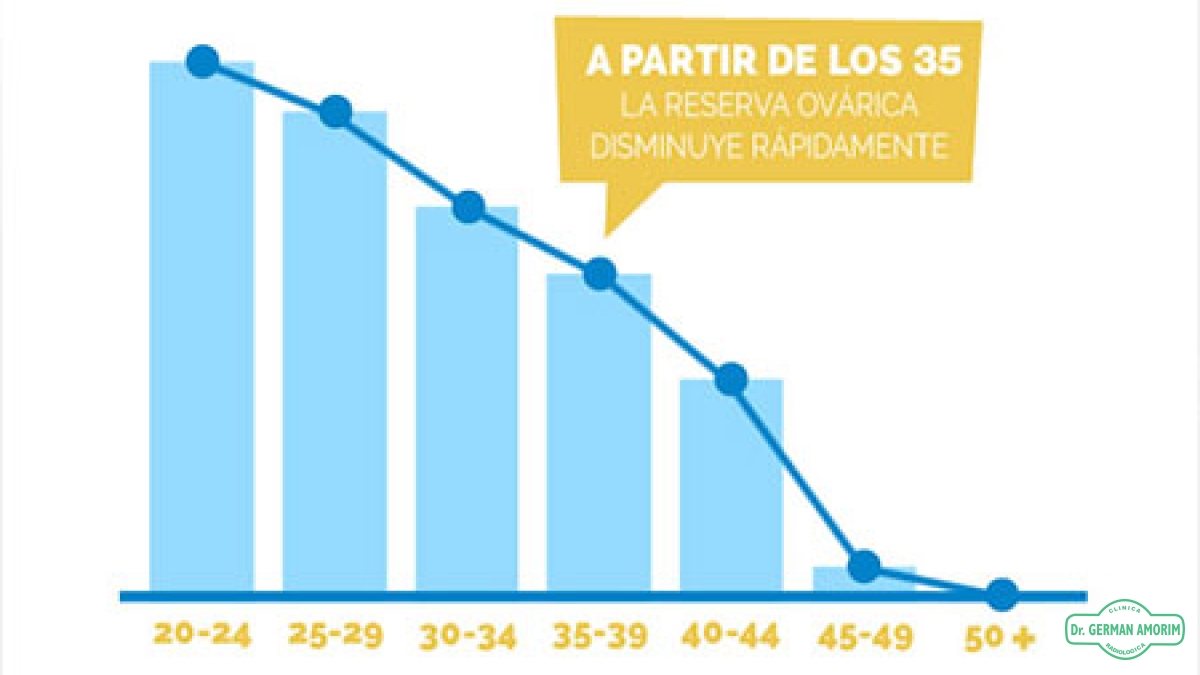

La reserva ovárica refleja el potencial fértil de la mujer.

A diferencia de los hombres, que producen espermatozoides a lo largo de toda la vida, las mujeres nacen con un número determinado de óvulos. Al llegar a la pubertad, la mujer comienza a ovular todos los meses; en el momento de la menopausia, la reserva de óvulos ha quedado agotada y consecuentemente la mujer pierde la fertilidad.